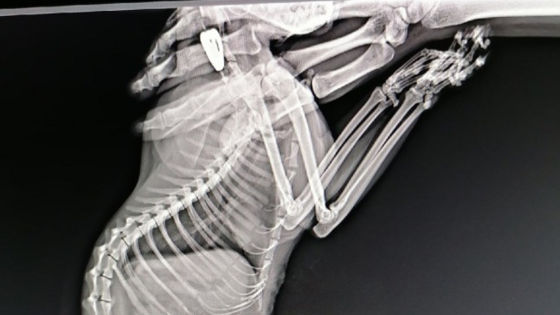

В красноярской ветеринарной клинике «Лимпопо» спасли кошку, в которую стреляли из пневматики, сообщают Дела.ру. Из тела животного вынули семь пуль

Инородные предметы разглядели на рентгеновском снимке. Как рассказывают сотрудники, к ним поступает все больше животных, пострадавших от рук человека. В комментариях красноярцы возмущаются поступком неизвестных хозяев. Напомним, что это не первый подобный случай. В прошлом месяце неизвестный убил кота, принадлежавшего тренеру по единоборствам Александру Герасимову. Поиски преступника до сих пор не окончены.